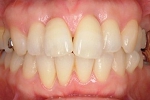

CASE3

前歯1本だけが出ています、矯正で治りますか?

(23歳/女性)↓

概要・担当医コメント:

前歯の唇側傾斜/マルチブラケット装置/非抜歯

動的治療期間15ヶ月(15回)/費用概算:60万円.

歯列アーチの形態修正に必要なスペースを微量のエナメル質の研磨により創生し,当初の計画通りに歯を移動させました.